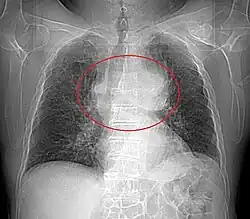

Présentation tomodensitométrique classique d'un thymome à un stade précoce (cercle rouge). À l'arrière, l'aorte, la veine cave supérieure et l'artère pulmonaire sont visibles en coupe.